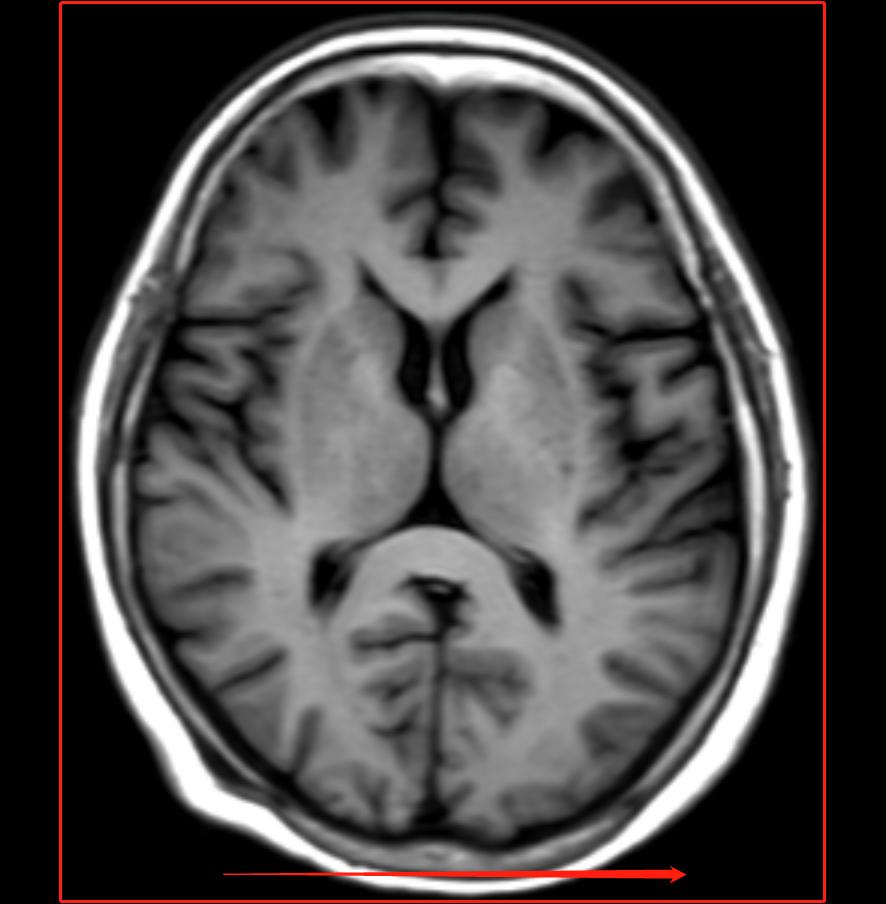

在磁共振扫描中,我们的相位编码通常设置在人体的短轴方向,为什么设置在短轴方向,因为相位编码在短轴方向上可以减少扫描时间,即使用部分FOV技术;

【图中左右方向为相位编码方向且使用矩形FOV】

【使用矩形FOV的目的是为了减少扫描时间,减少相位方向的矩阵也是为了减少扫描时间】

相位编码在短轴方向上还可以减少卷褶伪影,因为卷褶伪影最简单的理解就是选择的FOV没有把组织保全,如果选择在长轴就容易出现卷褶伪影;